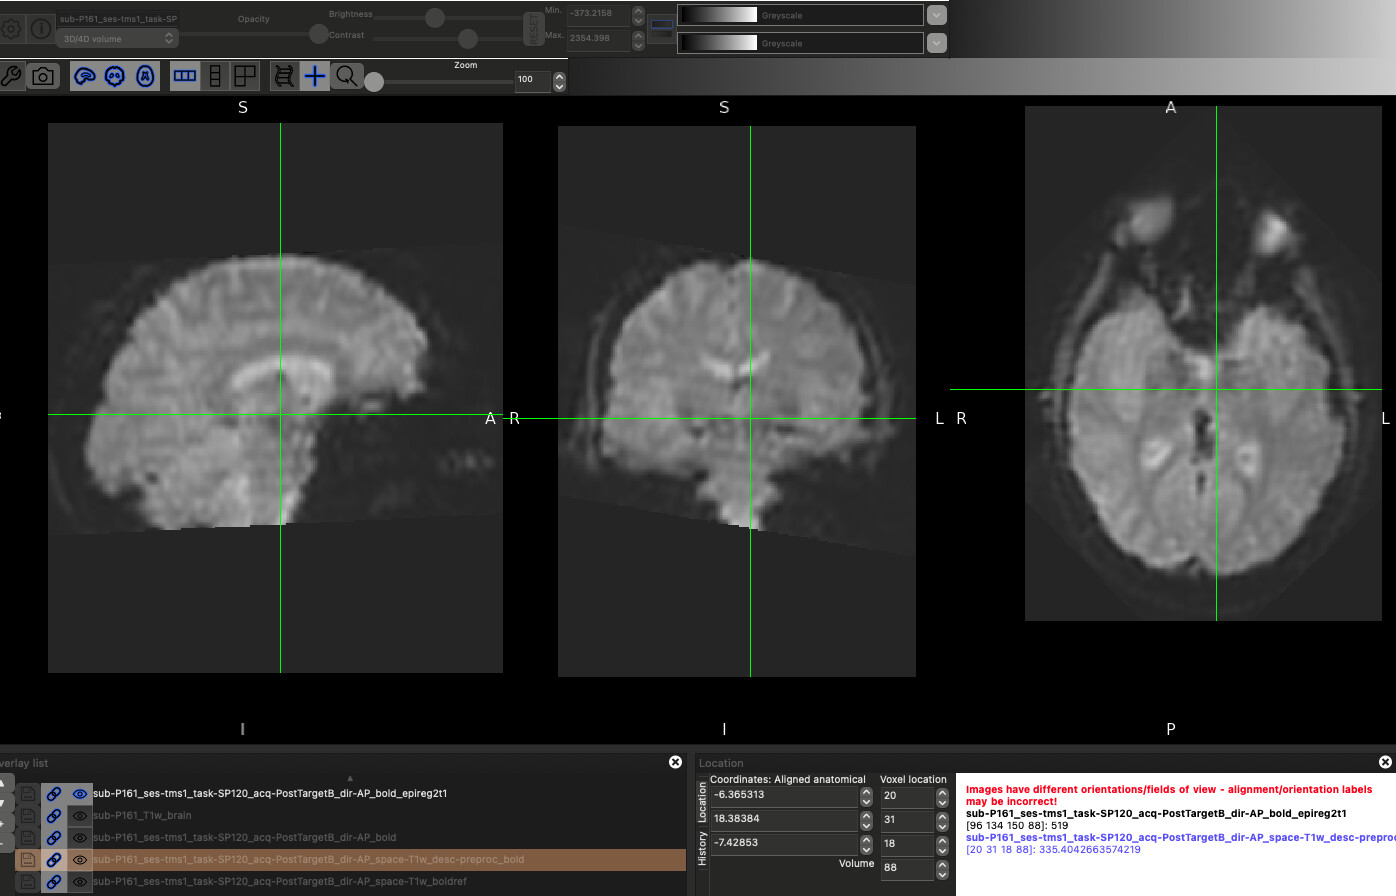

As an example, here is a raw image compared to the fmriprep preprocessing vs a quick epi_reg

Raw:

fmriprep:

epi_reg:

Essentially, I would like to use the epi_reg image as my fmriprep input rather than the raw image, but don’t know how to make that jive using the bids input format.